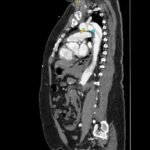

Acute aortic dissection is a life-threatening event caused by separation of the aortic layers that requires prompt management and surgical consultation. We present the case of a 53-year-old male who developed acute, severe chest pain radiating to his back at a community hospital and was transferred to a tertiary center for definitive surgical management. The patient’s aortic dissection was diagnosed via computed tomography angiography. He was started on rate-control and blood pressure medications, and was admitted emergently to the operating room. Emergency physicians should obtain immediate surgical consultation, promptly start medications for rate and blood pressure control, and administer analgesia in order to stabilize their patient and decrease the shear forces that would further propagate an aortic dissection.